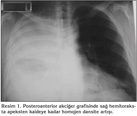

Klini?imize yat?r?ld???nda 39?C ate?, takipne (solunum say?s?: 28/dakika), perk?syonda sa? hemitoraksta matite ve osk?ltasyonda sa?da solunum sesi ?iddetinde azalma saptand?. Laboratuvar incelemesinde l?kosit 20.800/mm3, hemoglobin 12.3 g/dL, trombosit 433.000/mm3, sedimentasyon h?z? 100 mm/saat, aspartat aminotransferaz (AST) 52 U/L, alanin aminotransferaz (ALT) 54 U/L, oda havas?nda al?nan arteryel kan gaz?nda PaO2 51 mmHg bulundu. Posteroanterior akci?er grafisinde sa? hemitoraksta apeksten kaideye kadar homojen dansite art??? vard? (Resim 1). Pn?moni ve ampiyem tan?lar?yla antibiyotik tedavisi piperasilin-tazobaktam ile de?i?tirilirken olguya hemen bronkoskopi ve plevral ponksiyon yap?ld?. Endobron?iyal lezyon izlenmeyen olguda mikrobiyolojik de?erlendirmeler i?in ?rnekler al?nd?. Ultrasonografi (USG) e?li?inde yap?lan plevral ponksiyon sonucu 25 mL p?yden olu?an ?rnek al?nabildi. S?v?n?n biyokimyasal incelemesinde laktat dehidrogenaz (LDH) 29.300 U/L, total protein 5 g/dL, glukoz 10 mg/dL, adenozin deaminaz 76.3 U/L olarak saptan?rken, ?rne?in pH's?na teknik yetersizlikten dolay? bak?lamad?. Serbest plevral s?v? drene edilememesi nedeniyle ?ekilen toraks BT'de sa? hemitoraksta lok?lasyon g?steren masif plevral s?v?, plevral y?zeyde belirgin kal?nla?ma ve yayg?n mediastinal lenfadenopatiler g?r?ld? (Resim 2). G???s cerrahisi kons?ltasyonunda septik tablo nedeniyle cerrahi m?dahale d???n?lmedi. Sa? hemitoraksa vertebra ile skapula aras?na, toraks BT rehberli?inde ve USG e?li?inde ince plevral kateter (pl?rakan) tak?ld?. ?lerleyen g?nlerde toplam 1700 mL p?y bo?alt?ld?. Plevral s?v?n?n Gram boyamas?nda bakteri morfolojisi saptanmad? ve hasta ba??nda s?v?dan kan k?lt?r? besiyerine ekim yap?ld?. Al?nan bronkoskopik aspirasyon ve plevral s?v? ?rneklerinde bakteriyolojik, mikolojik, mikobakteriyolojik ?reme olmazken, patolojik inceleme sonucunda benign olarak de?erlendirildi. ?e?itli d?nemlerde al?nan kan ve balgam ?rneklerinde bakteriyolojik ?reme olmad?. Plevral kateter ile ilk bo?altma sonras? g?nde ortalama 200 mL plevral s?v? gelmeye devam eden olguda ???nc? g?nde, ate? kontrol alt?na al?nd?. Tedavinin yedinci g?n?nde tekrar ate?inde y?kselme ve l?kosit de?erlerinde d??me ba?lad?. Akci?er grafisinde d?zelme g?r?lmekle birlikte tekrarlanan toraks BT'de sa? hemitoraksta alt k?s?mda minimal lok?le s?v? oldu?u g?zlendi ve buradan USG e?li?inde ponksiyon denendi ama ?rnekleme yap?lamad?. Bu nedenle ?? g?n s?reyle mevcut plevral kateter yard?m? ile g?nl?k 250.000 ?nite intraplevral streptokinaz uygulanarak yap???kl?klar?n a??lmas? ve k???k lokalize alanlar?n drene olmas? planland? ancak minimum plevral s?v? d?n??? izlendi. Hemogram de?erleri giderek d??en olgunun l?kositi 1000/mm3 (n?trofil: %47, lenfosit: %49), hemoglobini 6.1 g/dL, trombositi 94.000/mm3, uluslararas? normalle?tirilmi? oran? (INR) 1.5 (0.91-1.09) ve aktive parsiyel tromboplastin zaman? (aPTT) 45.4 saniye (22.5-31.3) olarak saptand?. Hastaya eritrosit replasman? yap?ld?; antibiyotik tedavisi imipenem ve vankomisin ?eklinde tekrar d?zenlendi. Laboratuvar incelemelerinde AST 396 U/L, ALT 95 U/L, gamaglutamil transferaz (GGT) 127 U/L, LDH 4164 U/L, ferritin 5325 ng/mL (30-400), trigliserid 357 mg/dL (< 200) olarak saptand? (Tablo 1). Fizik muayenesinde v?cudunda yayg?n ?dem; g?vdesinde daha belirgin olmak ?zere t?m v?cutta ka??nt?l? mak?lopap?ler ve pete?iyal lezyonlar ile splenomegali geli?ti?i g?zlendi. ?nfeksiyonun tekrar alevlenmesi, laboratuvar de?erlerinin bozulmas?n?n nedeni olarak hastane k?kenli ya da farkl? etyolojide infeksiyon ve buna ba?l? sepsise gidi?, altta olas? hematolojik malignite ya da ba? dokusu hastal???nda atak d???n?ld?. Al?nan kan ve balgam ?rneklerinde ?reme saptanmad? ve serolojik testlerde; brusella, EBV, sitomegalovir?s (CMV), insan imm?nyetmezlik vir?s? (HIV), influenza, parainfluenza, respiratuar sinsityal vir?s (RSV) infeksiyonunu d???nd?recek bir bulgu g?zlenmedi (Tablo 2). Romatolojik belirte?leri normal saptanan olgunun kemik ili?i biyopsi ve aspirasyonu sonucu hipersel?ler kemik ili?i ve hemofagositoz; biyopside gran?lositer seride art??, aspirasyon preparat?nda gran?lositer seri hakimiyeti, %5 dolay?nda k???k lenfosit ve eritrosit fagositozu g?steren makrofaj saptand? (Resim 3, 4). Geli?en bu hemofagositoz sendromu tablosunun etyolojisi ve gen? sa?l?kl? bir ki?ide bu atipik infeksiyon seyrinin a??klamas? ?u ?ekilde yap?ld?; ilk a??r pn?moni ve ampiyem tablosuna sekonder geli?en hemofagositik sendrom, hastan?n imm?n direncini d???rerek hastane k?kenli infeksiyona yakalanmas?na neden olmu?tur. ?mipenem ve vankomisin tedavisi ile ate?i d??en, laboratuvar de?erleri d?zelen olguda; 21. g?nde tedavi sonland?r?ld?. Toplam 36 g?n hastanede kalan olgunun taburculu?undan bir ay sonraki kontrol?nde laboratuvar de?erleri normal olarak saptan?rken, akci?er grafisinde hafif d?zeyde plevral kal?nla?ma ve ?ekintiler d???nda patoloji g?zlenmedi.

Resim 1